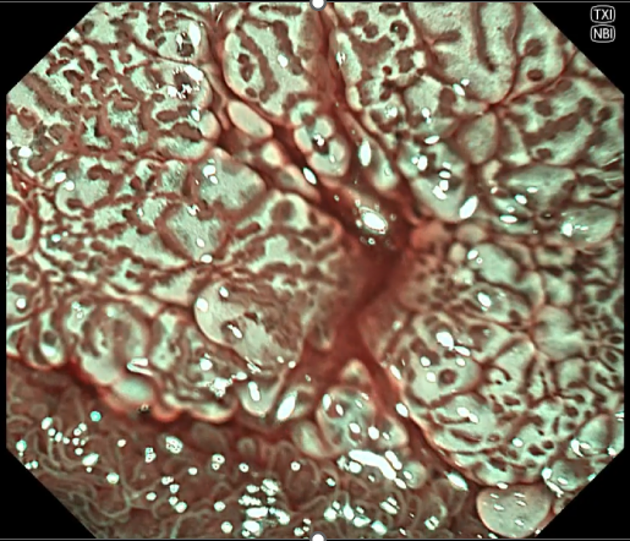

(2組)食道表在癌の拡大観察時の画像

NBI(左)よりもNBI+TXI(右)ではIPCLが強調されており、より明瞭に観察される。